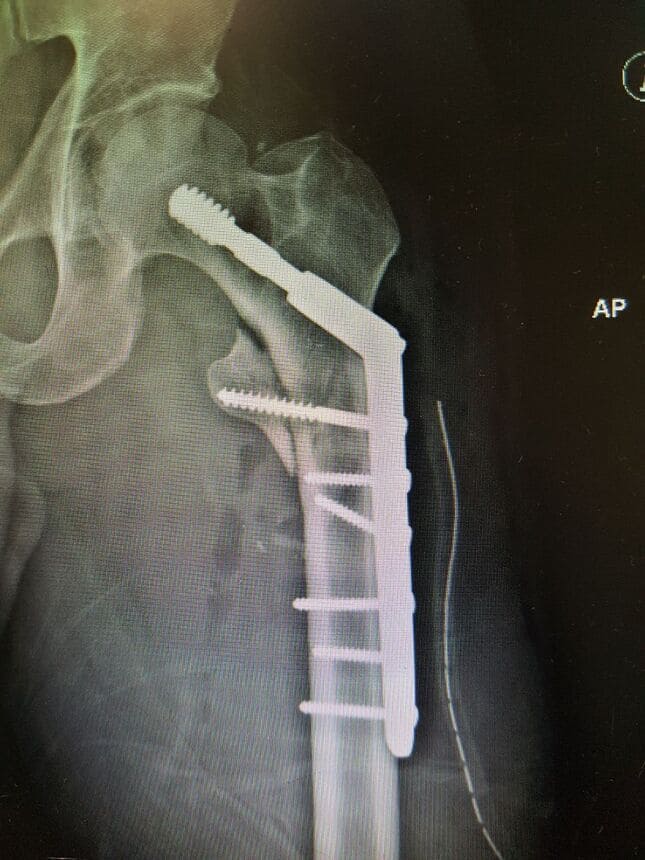

TRATAMIENTO DE FRACTURAS - GALERÍA DE IMÁGENES

Clavo de fémur